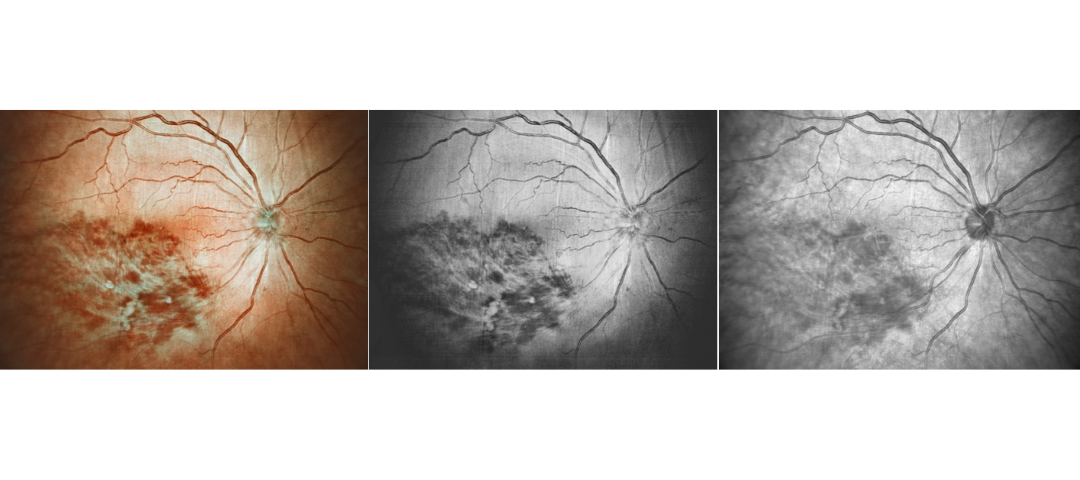

Optical Fundus Camera Get Retinal Layer

Traditional optical fundus cameras have a small field of view, generally 40 to 60 degrees, and can only see the retinal layer of the fundus, but cannot obtain a complete fundus image.

Scanning Laser Ophthalmoscope Obtain Retinal Layer and Choroidal Layer

Our scanning laser ophthalmoscope uses multi-wavelength laser scanning to penetrate the fundus, capture details of the retinal and choroidal layers, and obtain high-definition fundus images.

Retina Examination Under Cataracts

Examining fundus diseases through cataracts is a crucial topic in ophthalmology. Traditional fundus cameras cannot see through cataracts to capture fundus conditions. However, our DF600 scanning laser ophthalmoscope can penetrate moderate cataracts, providing a glimpse into the fundus and offering greater convenience for fundus examinations in patients with cataracts.

Diabetic retinopathy: post photocoagulation

Diabetic retinopathy: bleeding and microvascular lesions

Diabetic retinopathy: post photocoagulation

Diabetic retinopathy: bleeding, exudation, and post-photocoagulation

Diabetic retinopathy: bleeding

Diabetic retinopathy: bleeding and exudation

Diabetic retinopathy: vascular abnormalities, bleeding spots, and post-photocoagulation

Diabetic retinopathy: bleeding, exudation and choroidal vascular abnormalities

High blood pressure, venous obstruction, and bleeding